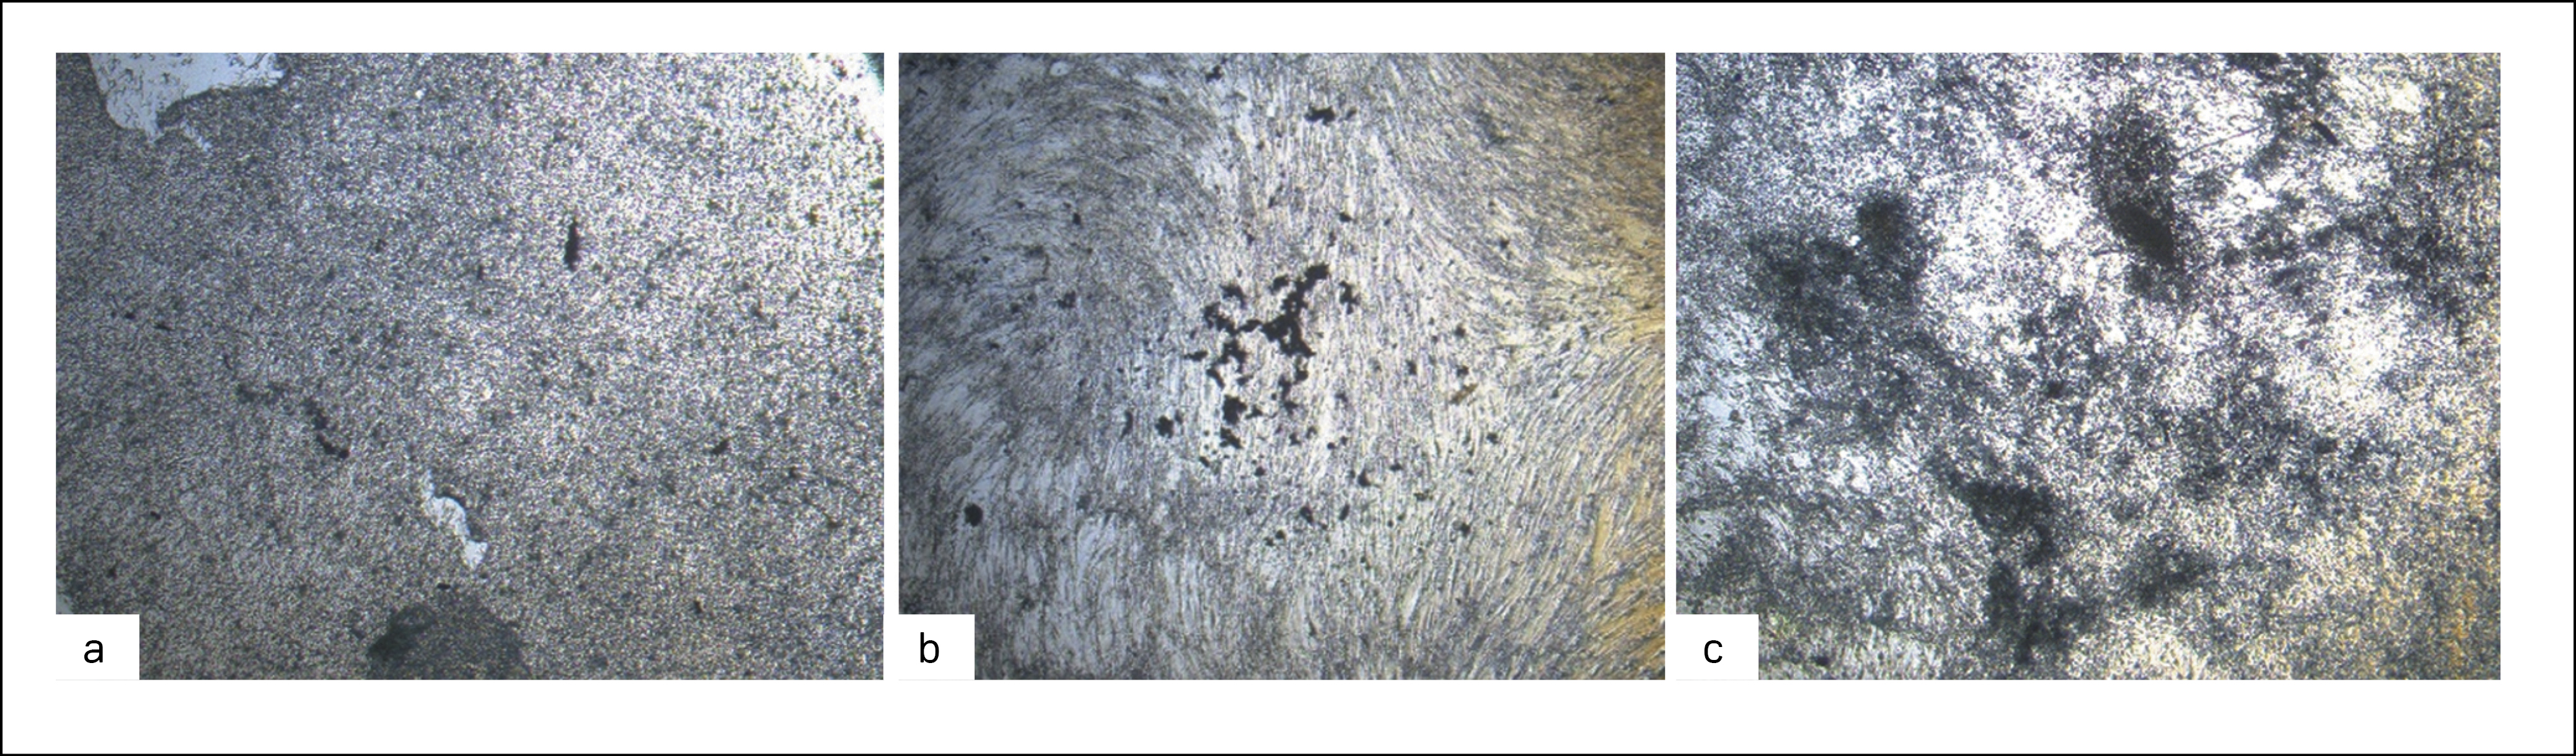

In the period from the 4th to the 7th day of cultivation in the OM (including addition of alPRP), there occurs re-differentiation of BM-MSC. In this period, the cells start expressing osteogenic markers, yet no calcium deposition starts in them. After 21 days of osteogenic differentiation, it was shown that the morphology of BM-MSC changed from spindle to cuboid. After Von Kossa’s staining of the specimens of differentiated cells with nitrate of silver, additionally, intracellular deposits of calcium phosphate were found (stained black). The changes were most manifested in the cells cultivated in the OM with 5% alPRP added (Fig. 4).

Figure 4. Von Kossa staining of BM-MSCs: (a) cells cultivated in CCM; (b) cells cultivated in OM; (c) cells cultivated in OM, supplemented with 5% alPRP. Images are taken at 100x magnification.

Рисунок 4. Окрашивание фон Косса КМ-МСК человека: (a) клетки, культивированные в ППС; (b) – клетки, культивированные в ОС; (c) – клетки, культивированные в ОС с добавлением 5% алПОРФТ. Изображения сделаны при 100-кратном увеличении.